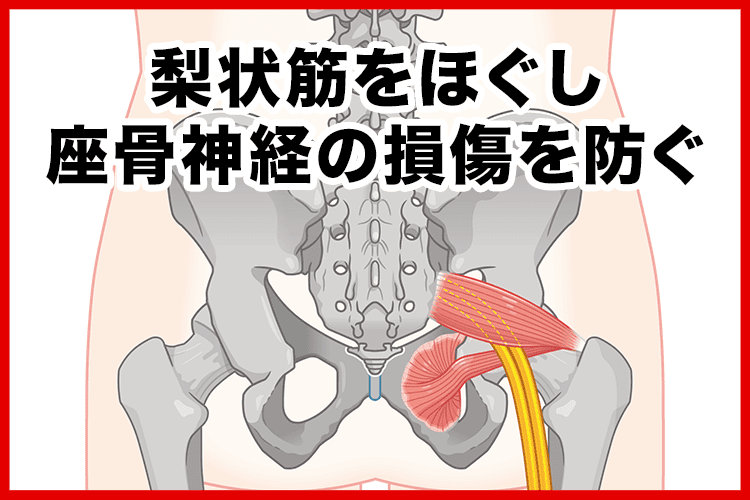

こんな痛みやしびれの原因は

梨状筋(りじょうきん)というおしりの奥の筋肉が硬くなること。

というのも

梨状筋のそばには坐骨神経が通っており、

梨状筋が硬くなると坐骨神経が圧迫されて傷ついてしまいます。

そして坐骨神経はおしり〜足先まで伸びているため、

損傷すると様々な箇所にしびれや痛みが現れるんです…

つまり、

これがしびれや痛みのメカニズム!

まずは1つ目の根本改善成分↓

※効果には個人差があります

この成分のおかげで梨状筋の硬直がほぐれ、

坐骨神経の損傷を防ぐことができます!